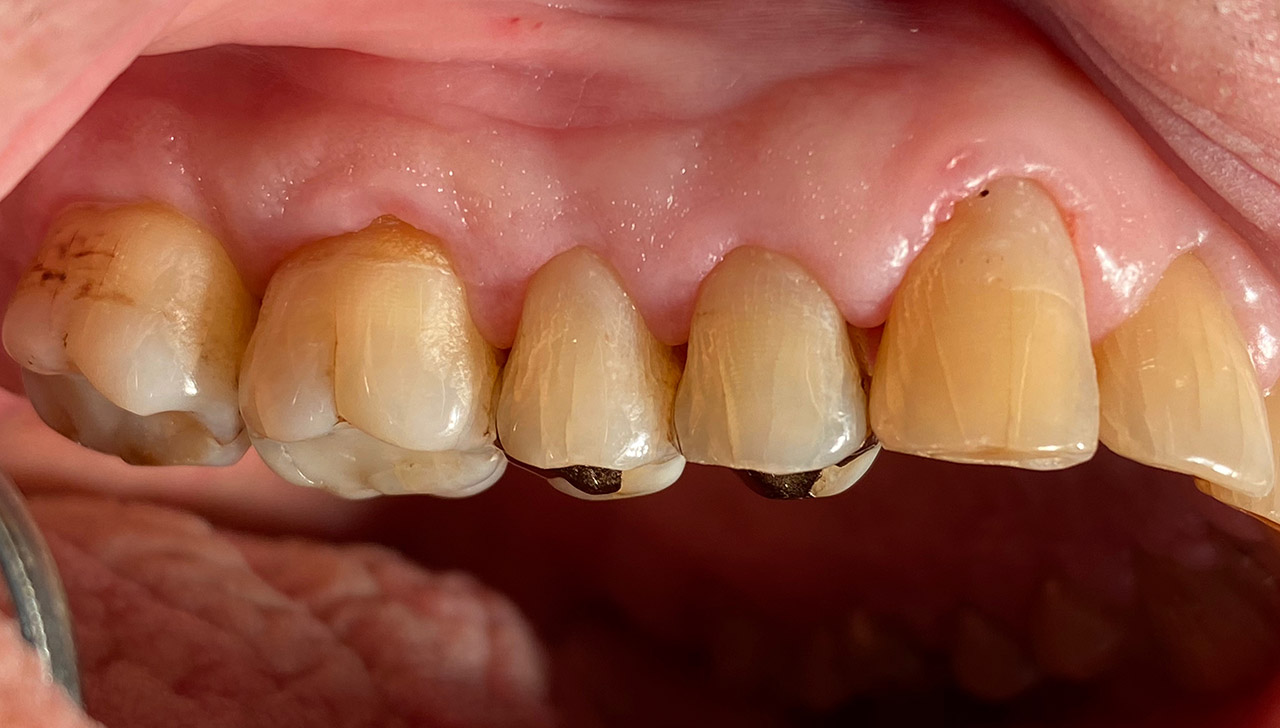

Parodontologie/Gingivahyperplasie:

Diagnose: Gingivahyperplasie durch Medikamente (Blutdrucksenker), unzureichende/nicht mehr mögliche Mundhygiene und überstehende Füllungen.

Therapie: Gingivektomie und anfinieren der Füllungen. Letztes Foto 1 Woche postOP.